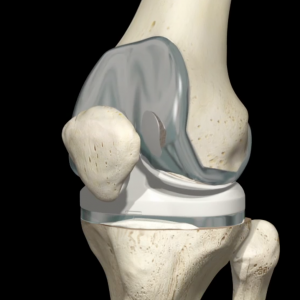

Το «ολικό εμφύτευμα κονδύλων» ή «αρθροπλαστική γόνατος επιφανείας» αποτελεί τώρα το σημείο αναφοράς για τις ολικές αρθροπλαστικές γόνατος παγκοσμίως.

Όπως και με την ολική αρθροπλαστική του ισχίου, η ολική αρθροπλαστική του γόνατος μπορεί να είναι τοποθετημένη με τσιμέντο ή χωρίς τσιμέντο. Η ορολογία αυτή αναφέρεται στον τρόπο της στερέωσης που χρειάζεται για να συνδεθεί η τεχνητή πρόθεση με το οστό.

Αναλυτικότερα, η στερέωση με τσιμέντο περιλαμβάνει την χρήση οστικού τσιμέντου (polymethylethacrylate, πολυμεθυλμεθακρυλικό) επιτρέποντας μια άμεση σταθερή πρόσφυση στο οστό του ασθενούς. Μία πρόθεση χωρίς τσιμέντο χρειάζεται επικάλυψη με ειδική διαμόρφωση ή επίστρωση (για παράδειγμα πορώδες μέταλλο ή υδροξυαπατίτη) προκειμένου να σταθεροποιηθεί στο οστό του ασθενούς. Ο στόχος και στις δυο περιπτώσεις είναι η ενσωμάτωση, έτσι ώστε να επιτευχθεί μια σταθερή στερέωση.

Το θεωρητικό προτέρημα ενός σχεδιασμού χωρίς τσιμέντο είναι ότι κάνει την επέμβαση αναθεώρησης πιο εύκολη αν ποτέ χρειαστεί. Θεωρείται ότι οι σχεδιασμοί χωρίς τσιμέντο είναι πιο εύκολο να αφαιρεθούν, στην πράξη όμως δεν είναι πάντοτε αυτό αληθινό. Οι σχεδιασμοί χωρίς τσιμέντο μπορεί ορισμένες φορές να είναι πολύ δύσκολο να αφαιρεθούν κατά την διάρκεια μιας αναθεώρησης. Αυτό παρατηρείται ειδικότερα κυρίως σε περιπτώσεις που έχει πραγματοποιηθεί μια πολλή καλή οστεοενσωμάτωση. Αντίθετα η αφαίρεση της πρόθεσης από το τσιμέντο είναι μια σχετικά εύκολη διαδικασία. Η στερέωση της αρθροπλαστικής γόνατος με τσιμέντο έχει καλύτερα αποτελέσματα και θεωρείται ακόμη η καλύτερη επιλογή.